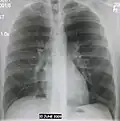

The discovery of x-rays made it possible to determine the anatomic type of pneumonia without direct examination of the lungs at autopsy and led to the development of a radiological classification. Early investigators distinguished between typical lobar pneumonia and atypical (e.g. Chlamydophila) or viral pneumonia using the location, distribution, and appearance of the opacities they saw on chest x-rays. Certain x-ray findings can be used to help predict the course of illness, although it is not possible to clearly determine the microbiologic cause of a pneumonia with x-rays alone.

Normal lateral CXR -

Right lower lobe pneumonia as seen on a lateral CXR